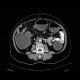

The most prominent finding in this examination was massive dilation of the colon with air-fluid levels indicating bowel obstruction (ileus). Its cause can be tracked down to sigmoid, where a tumorous thickening of the wall with extension into the mesosigmoid and involvement of local lymph nodes can be found. Small bowel loops remain relatively undistended thanks to competence of the ileocecal valve.